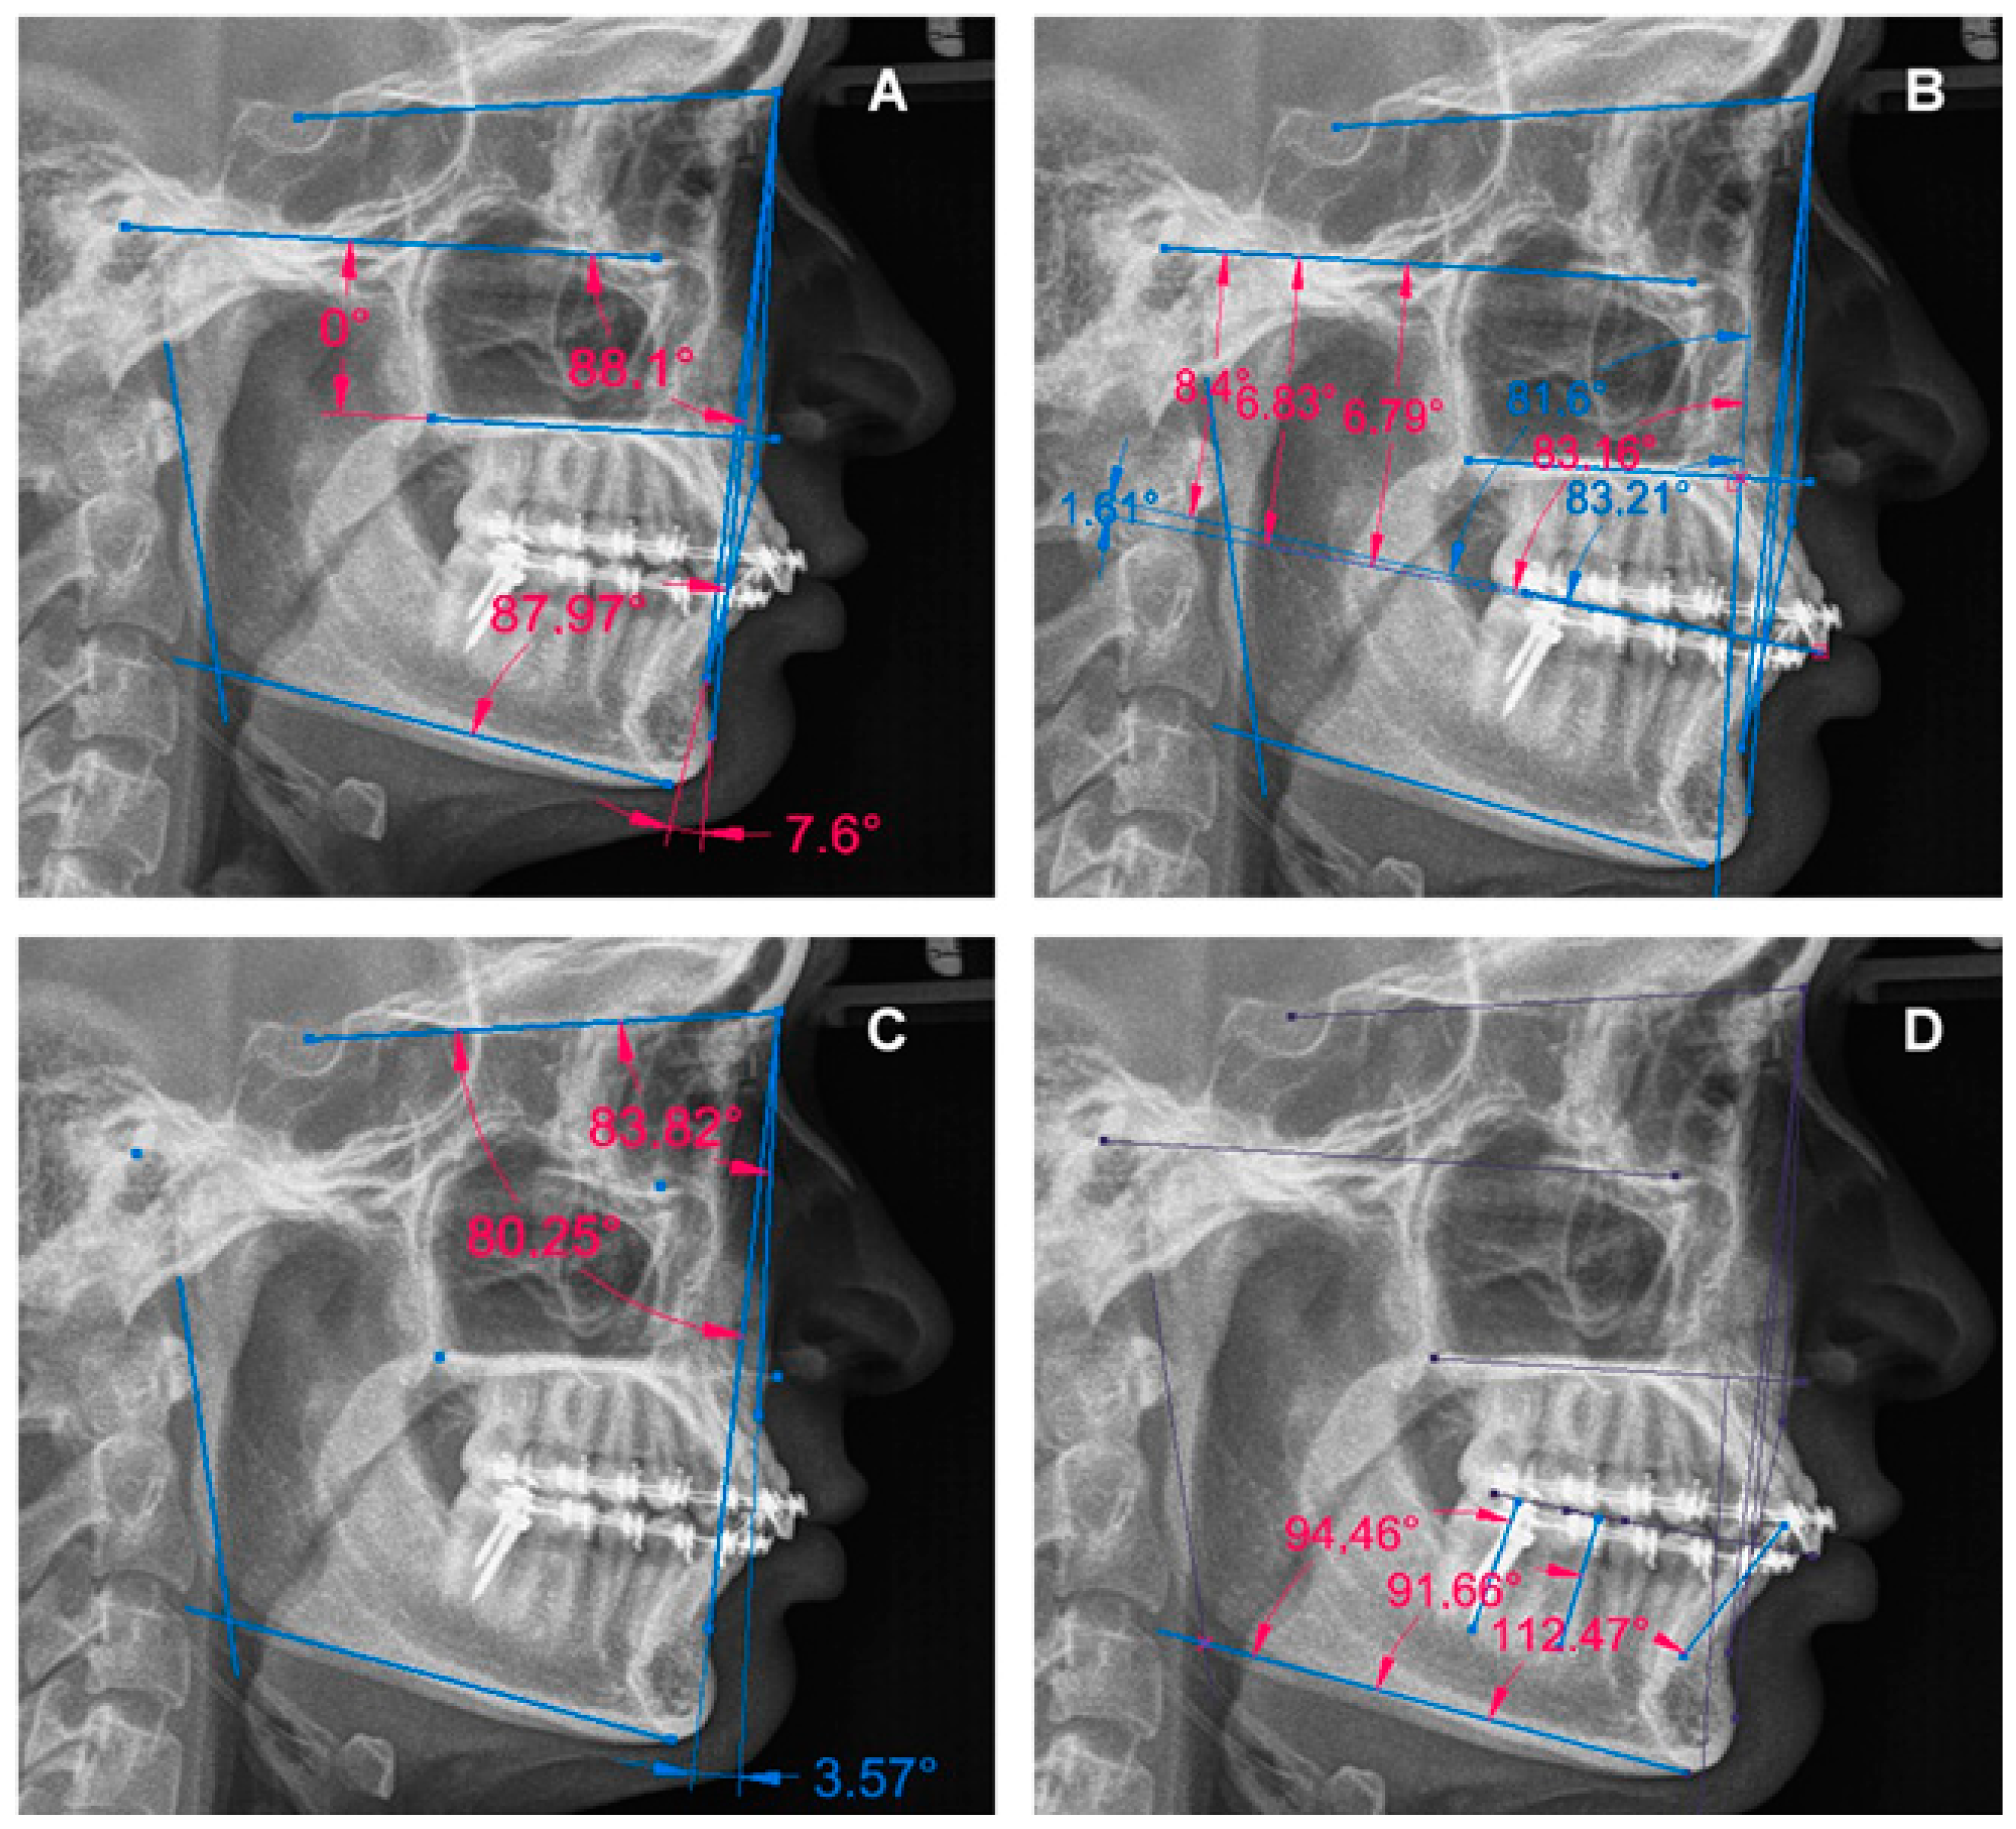

3. Results

3.2. Report of the Specific Characteristics of the Cases